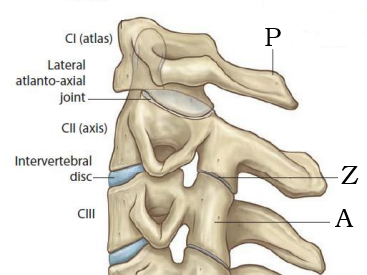

Arch of altlas.

Atlanto-axial joint.

Body of axis.

Lateral mass of axis

Inferior articular process; Superior articular process